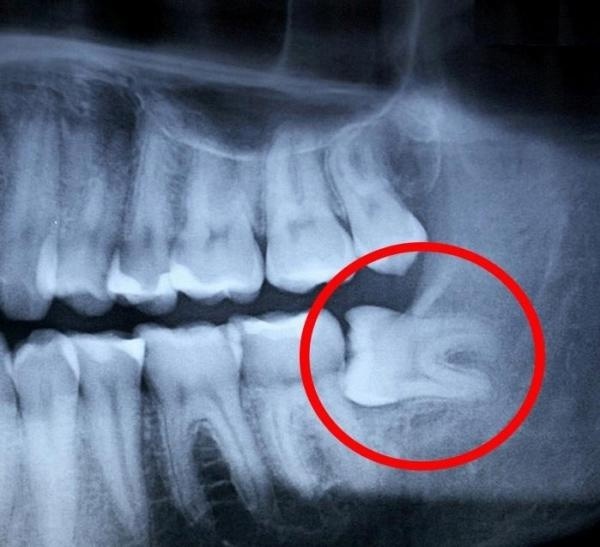

Частичное прорезывание. Зуб может не выйти на поверхность и находиться в десне или вылезти частично.

Дистопия. Этот термин означает неправильное расположение зубов в ряду. Они могут криво расти и выступать из зубного ряда. Это приводит к травмированию, воспалению мягких тканей десен, щек, языка.

При решении вопроса, удалять зуб мудрости или нет, врач должен провести тщательный осмотр и при необходимости направить пациента на дополнительную диагностику - например КТ.